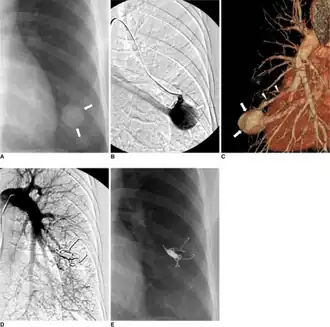

Treatment for brain AVMs can be symptomatic, and patients should be followed by a neurologist for any seizures, headaches, or focal neurologic deficits. AVM-specific treatment may also involve endovascular embolization, neurosurgery or radiosurgery.[6] Embolization, that is, cutting off the blood supply to the AVM with coils, particles, acrylates, or polymers introduced by a radiographically guided catheter, may be used in addition to neurosurgery or radiosurgery, but is rarely successful in isolation except in smaller AVMs.[22] Gamma knife may also be used.[23]

Treatment of lung AVMs is typically performed with endovascular embolization alone, which is considered the standard of care. [24]